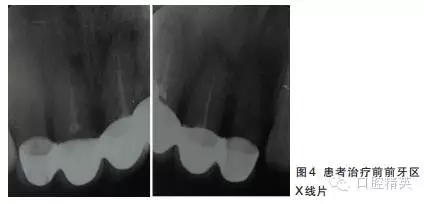

12~22烤瓷聯(lián)冠修復,冠邊緣不密合,齦緣外形不協(xié)調,牙齦紅腫,22烤瓷冠崩瓷。根管治療不完善,牙齦根尖部位有瘺管,X線影像顯示11、21根尖有陰影。

董艷梅教授:修復前如有以下情況,應考慮進行根管再治療:①X線片顯示前次根管治療不完善;②X線片顯示患牙根尖周新增病變或根尖周病變范圍擴大或未見縮小;③患牙在前次根管治療后長期有癥狀或臨床體征。